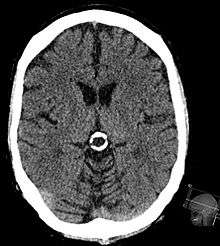

Pineal gland cyst

A pineal gland cyst is a usually benign (non-malignant) cyst in the pineal gland, a small endocrine gland in the brain. Historically, these fluid-filled bodies appeared on 1-4% of magnetic resonance imaging (MRI) brain scans, but were more frequent at death, seen in 21-41% of autopsies.[1] A 2007 study by Pua et al. found a frequency of 23% in brain scans (with a mean diameter of 4.3 mm).[1]

It was once believed that smaller cysts (less than 5.0 mm) were usually asymptomatic, but for larger cysts (greater than 5.0 mm), symptoms could include headache, unexpected seizures, visual disturbances, memory loss, cognitive decline, muscle fasciculations, nausea, weakness, fatigue, light sensitivity, tinnitus, circadian rhythm dysfunction, or hydrocephalus if the cyst impinged on the superior colliculi or caused obstruction of the cerebral aqueduct. Newer research shows that the size of the cyst does not necessarily correlate to the presence of symptoms. In some cases, it will need to be removed before life-threatening situations occur.